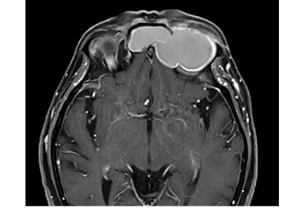

Se le solicita una tomografía de nariz y senos paranasales donde encontramos el velamiento total de ambos senos frontales, ocupados por densidad de partes blandas, adelgazamiento, erosión y destrucción de las paredes superior, posterior e inferior del seno frontal izquierdo con invasión de órbita izquierda y desplazamiento ocular hacia abajo y afuera (Figura 2), también se solicita una resonancia magnética contrastada constatándose la ocupación de ambas digitaciones del seno frontal por gran mucocele, que no restringe a la difusión y muestra tenue realce periférico; con remodelado óseo y efecto de masa sobre las estructuras adyacentes, en especial sobre el globo ocular izquierdo generando proptosis, realce meníngeo laminar regional a nivel del aspecto frontal izquierdo, sin edema parenquimatoso ni focos de abscesos y nervios ópticos de espesor y contornos conservados, sin realce patológico (Figura 3).

Lo que se espera encontrar con las técnicas de diagnóstico imagenológico son, con la tomografía, un adelgazamiento, erosión e incluso destrucción de las paredes óseas, principalmente la pared posterior debido a su delgadez, poniendo en comunicación las estructuras adyacentes con el seno afecto, el cual se encuentra ocupado por una densidad de partes blandas, homogénea sin aire que no realza con el contraste. La resonancia magnética nos sirve para diferenciarlos de los tumores nasosinusales y delimitar el contacto con estructuras adyacentes, los hallazgos en T1 encontramos una masa de contenido hipointenso con una delgada línea periférica hiperintensa. Todos estos hallazgos coinciden con los hallazgos imagenológicos del caso presentado8-10.